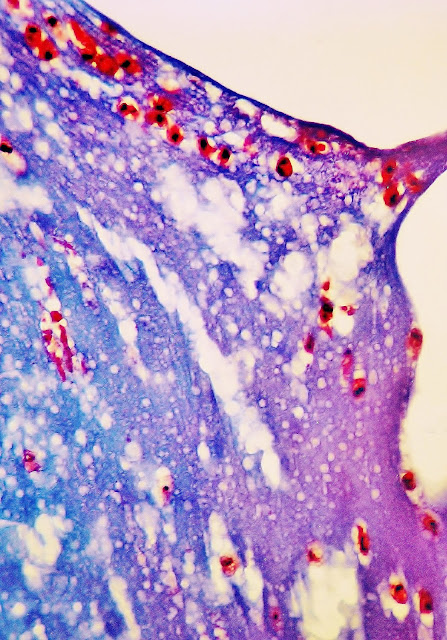

123.1A.-Fig.6.-Muerte súbita por picadura de abeja. Tráquea. Moco traqueal. Eosinófilos.

La luz traqueal presentaba abundante moco que -al examen microscópico- mostraba la composición que se observa en la fotografía, expresiva de la naturaleza anafiláctica de la muerte del sujeto.

El moco -teñido de azul- se encuentra perforado por abundantes burbujas de aire, de diferentes tamaños. En el seno del tapón de moco se detectan numerosos leucocitos polimorfonucleares, eosinófilos, cuyos núcleos se tiñen de color negro -por la hematoxilina férrica- y de rojo intenso, los citoplasmas, por la fuchsina.